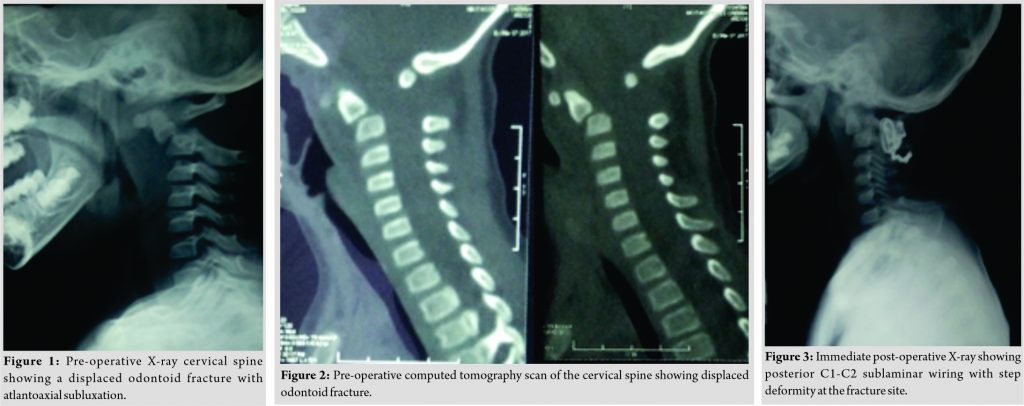

A 2-year-old female child was brought to our tertiary care center with alleged history of road traffic accident followed by complaint of inability to hold the neck upright. She had to support her chin with her wrists. Examination revealed restricted neck range of movements with tenderness at the craniocervical junction. Her neurological examination was normal with normal tone maintained in all the four extremities. Radiographs (Fig. 1) and computed tomography (CT) scan of the cervical spine (Fig. 2) revealed a displaced fracture of the odontoid synchondrosis with anterior subluxation of C1 over C2 vertebra.The patient was immobilized with a Philadelphia collar. In view of significant displacement of the odontoid with associated atlantoaxial subluxation, adecision was taken to perform reduction and posterior atlantoaxial fusion using sublaminar wiring. The procedure was performed through a posterior approach. Sublaminar wires were passed under C1 posterior arch and C2 lamina, and reduction was done under fluoroscopy guidance. A small diameter mesh cage filled with hydroxyapatite crystals was placed between the C1 posterior arch and the C2 lamina to maintain C1-C2 vertebral alignment and aid fusion. Surgery was carried out without any complications and postoperatively, she was maintained in Philadelphia collar for a period of 8 weeks. The post-operative period was uneventful. Her immediate post-operative radiography revealed a step deformity with angulation at the fracture site (Fig. 3).

Case Report: We report a case of a displaced odontoid synchondrosis fracture in a 2-year-old girl with anterior subluxation of C1 over C2 vertebra. This was treated with a posterior atlantoaxial fusion using sublaminar wiring. Immediate post-operative radiography showed partial reduction of the displaced odontoid fragment on C2 body with residual step deformity with angulation at the fracture site. Follow-up at 1 year showed excellent remodeling.

Cervical spine injuries in the children are unusual, and an incidence rate of 1.5–3% of all the spinal fractures has been reported [1,2]. The cartilaginous end plate between the dens and the body of the axis usually ossifies at the age of 5–7 years. This anatomical characteristic has been attributed to odontoid synchondrosis fractures in young children [3,4,5]. However, odontoid process fractures are rare in children and only few cases have been reported in theliterature [3,6]. We report a case of a displaced odontoid synchondrosis fracture in a 2-year-old girl with anterior subluxation of C1 over C2 vertebra. This was treated with a posterior atlantoaxial fusion using sublaminar wiring. Immediate post-operative radiography showed partial reduction of the displaced odontoid fragment on C2 body with residual step deformity with angulation at the fracture site. Follow-up at 1 year showed excellent remodeling.